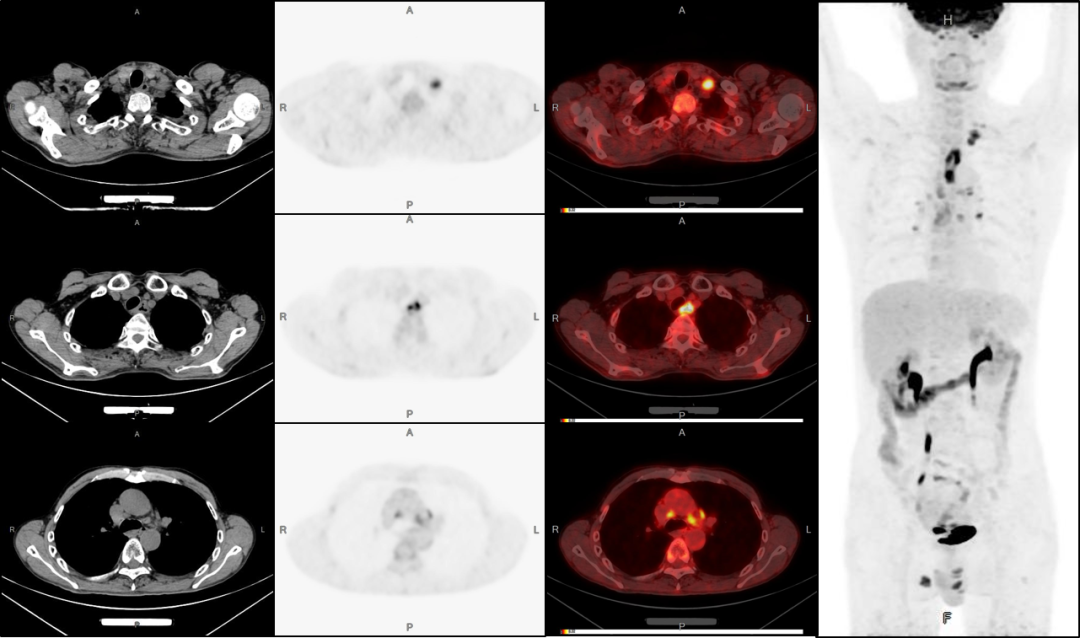

病例2:男性,51歲,反復(fù)咳嗽無痰半年余;發(fā)現(xiàn)左側(cè)鎖骨內(nèi)腫塊數(shù)月余。

3、雙股骨上段轉(zhuǎn)移可能。